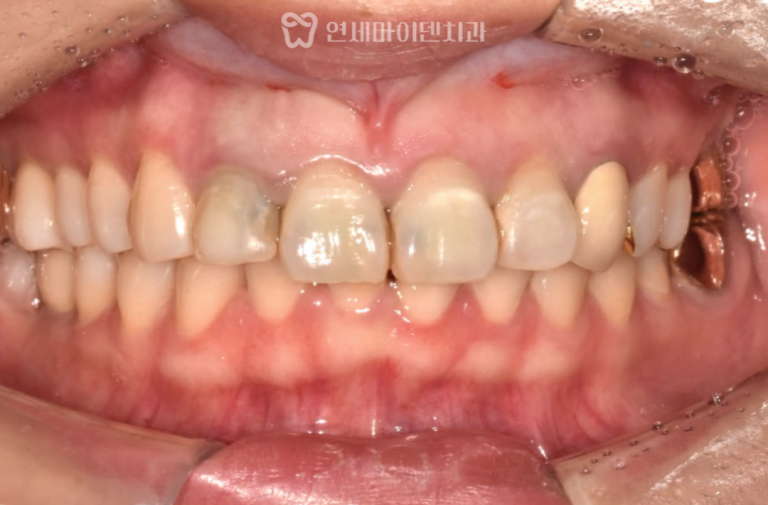

철저한 염증 제거와 이식재 충전을 통해

임플란트가 안정적으로 골유착되었으며

잇몸도 정상적으로 회복되었습니다.

치료 후 안정적인 초기 고정이 확보되었으며,

양측 교합의 균형이 회복되었습니다.

4개월 후 잇몸과 뼈가 충분히 재생되어

상악동과 연계한 지연 임플란트를 식립하여 마무리하였습니다.